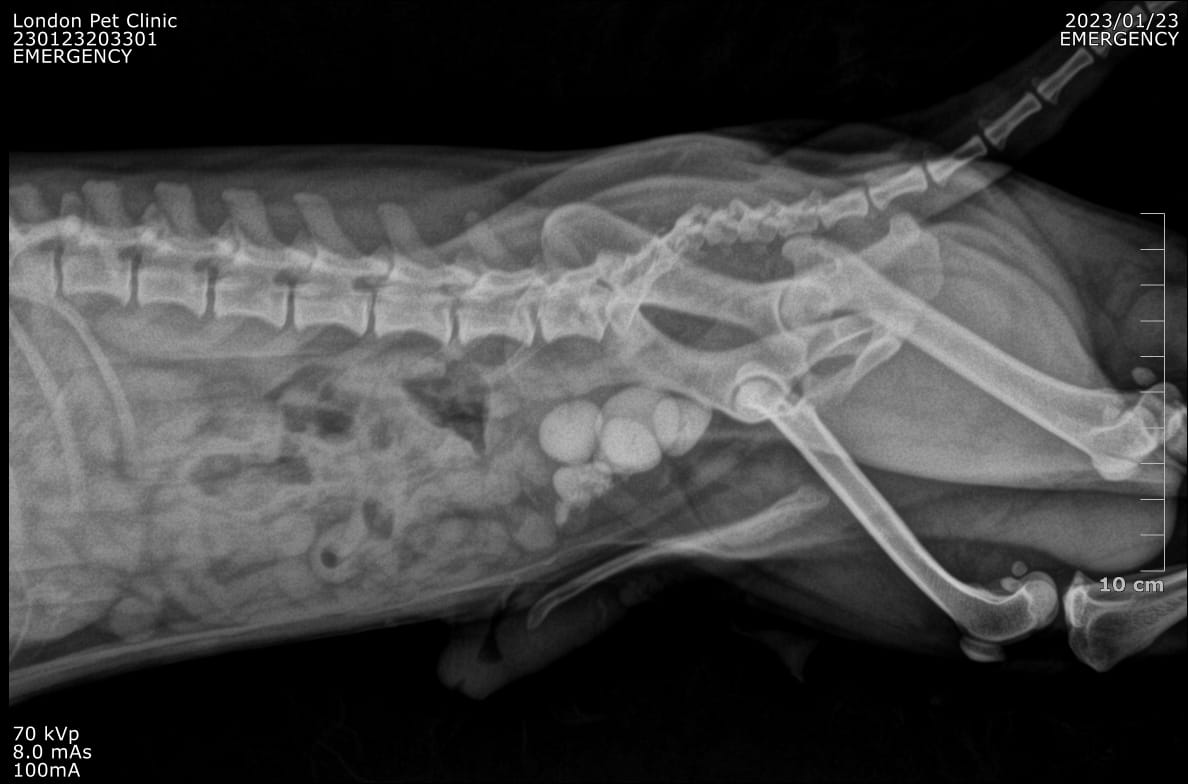

Abdominal Radiographs: Multiple radiopaque uroliths visible in the bladder

Multiple radiopaque uroliths visible in the bladder